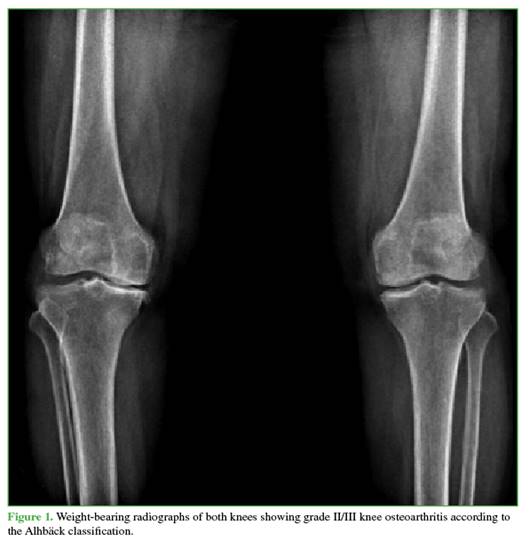

A 68-year-old male surgeon presented with degenerative joint disease and symptomatic genu varum (Figure 1).

Recently, he had to increase his analgesic medication and limit walking.

In previous consultations, intra-articular hyaluronic acid injection and prosthetic arthroplasty had been proposed.

At the time of evaluation, the patient reported having declined both options: a) he refused injection therapy because of progressive malalignment of the knee, and b) he was not yet willing to undergo prosthetic arthroplasty, as he did not perceive a significant limitation in his daily or professional activities.